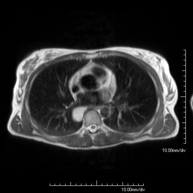

- Tòrax

- RM del Mediastí

Prova diagnòstica no invasiva que consisteix en l'obtenció d'imatges d'alta definició anatòmica del mediastí mitjançant l'ús d'un camp electromagnètic i ones de ràdio (amb un emissor i un receptor). No utilitza radiació ionitzant. El mediastí és la part central de la caixa toràcica que inclou el tim, els grans vasos (aorta toràcica, vena cava inferior i superior, etc.), el cor, la tràquea i els bronquis principals, els ganglis limfàtics mediastínics i hilars, l'esòfag, etc. Està especialment indicada en lesions mediastíniques per diferenciar si són quístiques o sòlides, en el diagnòstic diferencial de les lesions del mediastí anterior, etc. De vegades s'ha d'emprar contrast paramagnètic (Gadolini) per completar l'estudi. - RM Tòrax

Prova diagnòstica no invasiva que consisteix en l'obtenció d'imatges d'alta definició anatòmica del tòrax mitjançant l'ús d'un camp electromagnètic i ones de ràdio (amb un emissor i un receptor). No utilitza radiació ionitzant. Està indicada en aquelles lesions pulmonars en les quals s'ha de descartar si hi ha infiltració del mediastí o de la paret toràcica, per diferenciar si una lesió toràcica és sòlida o quística, etc. En alguns casos caldrà emprar contrast paramagnètic (Gadolini) per completar l'estudi. - RM de Paret Toràcica